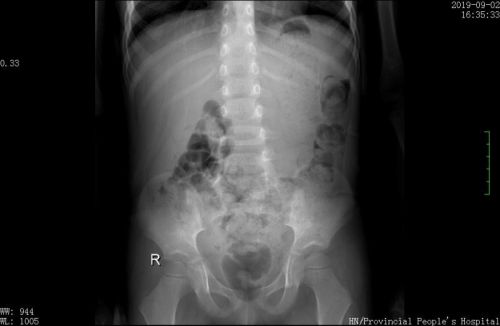

当地捷克论坛 x光显示,10颗磁力珠在胃里连成串。

2岁的小猛(化名)家住湖南邵东市,几天前,小家伙在和哥哥玩磁力球时,因为好奇心作祟,竟然接连吞下好几颗。当家长发现珠子少了询问大儿子时,才知道是被小猛吞进腹中,于是赶紧带他到当地捷克论坛 做检查。照X片后发现,由于磁力作用,10颗珠子在胃里首尾相连吸附在一起,形成一条“手串”。